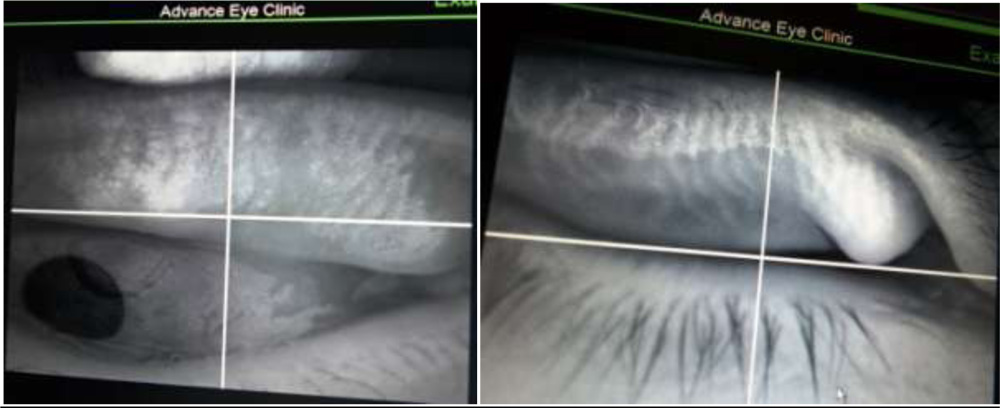

We tried to visualize the MGs by the infra red imaging using autorefractomer (Topcon RM8900), non contact tonometer (CT 80 Topcon), fundus camera (Zeiss), Zeiss  IOL master 500, specular miscroscope ( Topcon SP-3000p), ATLAS 9000 topographer and Visante AS-OCT which we have in our hospital. The images obtained were good enough to visualize the morphological features of MGs in these MGD eyes. We noted gland tortousity, shortening of the glands, broadening of the glands and gland drop-outs to various extent in many eyes. The images obtained by autorefractometer, IOL master, specular microscope, fundus camera, corneal topographer and Visante AS-OCT were better than those obtained by non-contact tonometer (NCT). The central shadowing of NCT while noting the MGs obscures the full visualization of MGs. The sample images obtained from these above mentioned instruments are as follows:

Visante AS-OCT: